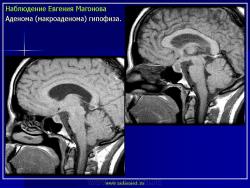

ГМ. Патология области турецкого седла. Набор изображений. +

Патология области турецкого седла.

впервые настолько глубокие изменеия турецкого седла, что даже не требуется дообследование.